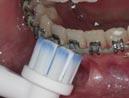

Several studies have investigated the efficacy of manual and electric toothbrushes (Figures 2a and 2b). Some authors have found electric to be more effective than manual models,5 while others could not reproduce these conclusions. Conversely, the opposite has also been demonstrated.6 A recent systematic review and meta-analysis on this topic emphasised the equivocal nature of the current evidence.7 Various manual toothbrush designs have also

been investigated (Figures 3a and 3b). Research has found no significant difference in plaque removal effectiveness between different manual designs.8 There is some evidence that new models of electric toothbrushes may be more effective than traditional ones.

The current consensus is that there is insufficient evidence to advocate for the use of electric over manual toothbrushes, or for any one manual design, for improving plaque control in FA patients. Therefore, the dental team should aim to improve patients’ knowledge and awareness, in conjunction with other aids, rather than focusing on the type of brush used.